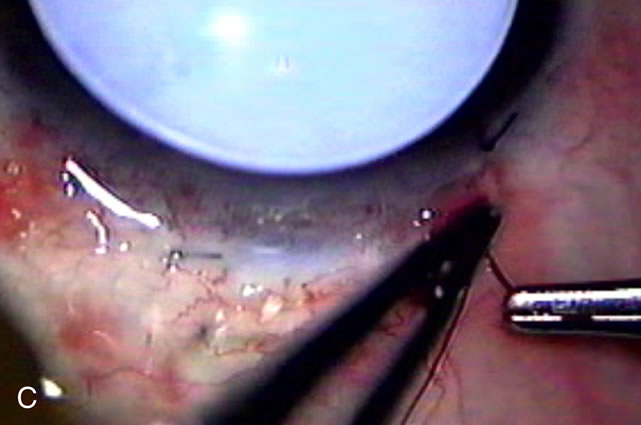

Fig. 7. Phacotrabeculectomy adjacent to a failed filter in cataractous eye. The ability to combine small-incision cataract extraction with trabeculectomy all through the same incision adjacent to the failed filter allows the surgeon to work in a familiar superior area. Avoiding incisions into the existing bleb decreases conjunctival buttonholes, hypotony, operating room time, and subconjunctival bleeding. A. Appearance of failed bleb with exposure of superior temporal quadrant gained with a corneal traction suture. B. Prepare a limbus-based conjunctival flap and a scleral flap. C. This bleb is at high risk to fail again justifying the need for MMC, 0.2 mg/cc applied on a pledget for 4 minutes. D. Insert the keratome and perform phacotrabeculectomy in the usual fashion.